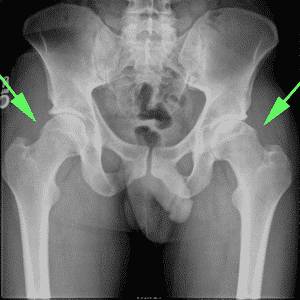

Для оценки правильности развития суставов у новорожденного можно обратить внимание на несколько признаков:

- анализируется симметрия кожных складок на бедрах и под ягодицами; различия в уровнях складок могут указывать на задержку в развитии сустава;

- проверяется амплитуда отведения бедра. Для этого ноги сгибают и прижимают к животу, а затем аккуратно разводят в стороны. Нормой считается легкость движений, в то время как при наличии патологии движения будут ограничены;

- обращается внимание на наличие щелчка при движении. Если щелчок присутствует, это может свидетельствовать о том, что головка бедра недостаточно зафиксирована в еще не полностью сформированной впадине.

При выявлении хотя бы одного из этих признаков рекомендуется провести ультразвуковое исследование и сонографию.